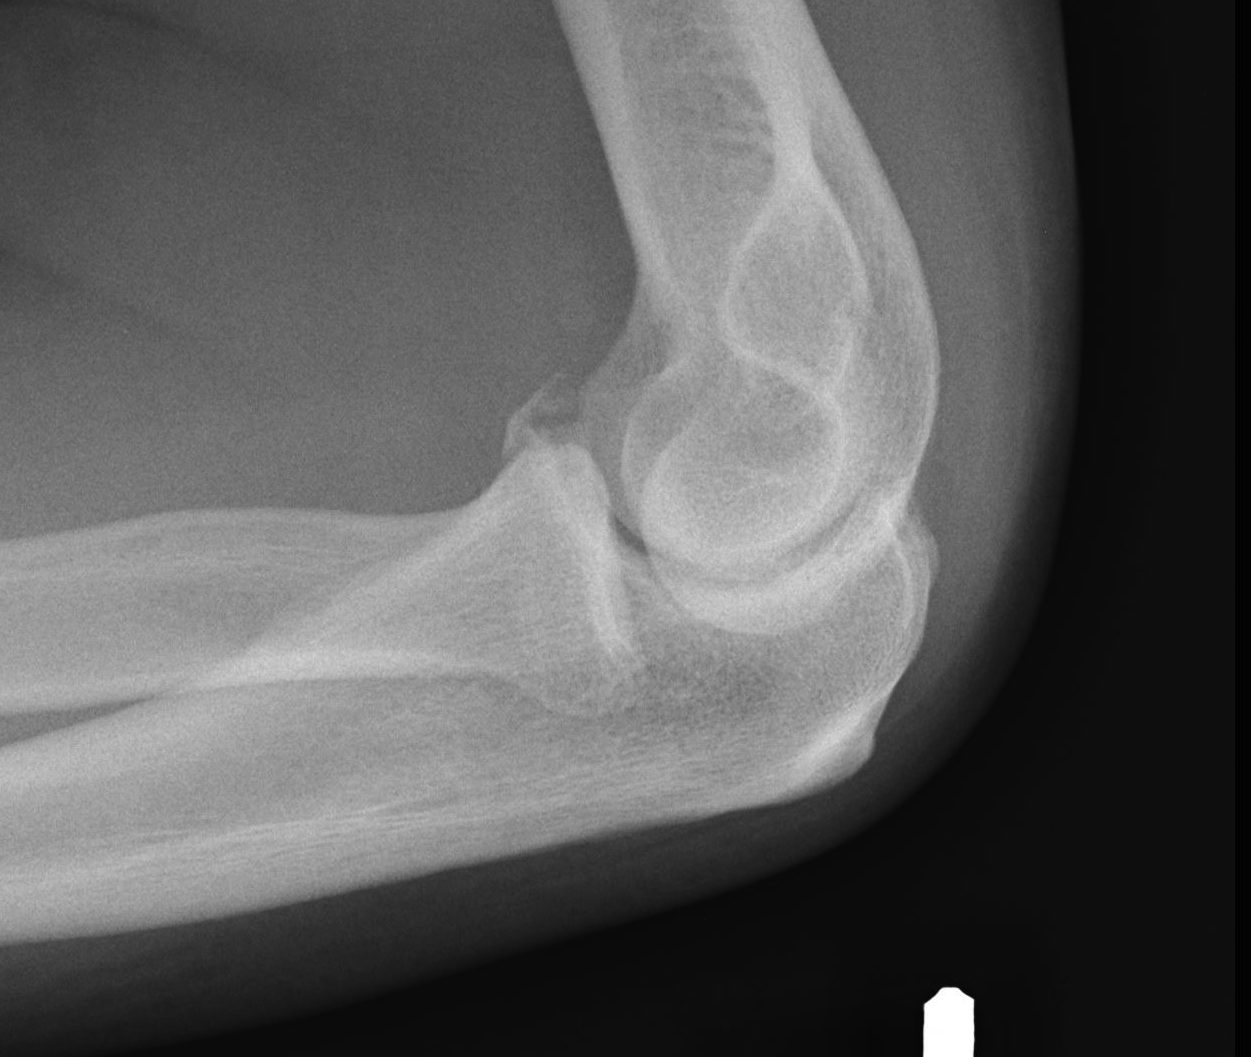

Regan and Morrey classification of transverse coronoid fractures

Elbow stability related to size of coronoid fragment

| Type I | Type II | Type II |

|---|---|---|

| Small coronoid process fracture | 50% of coronoid process | > 50% coronoid process |

| Usually stable |

Capsular attachment Elbow unstable |

Capsule + MCL attachment Elbow unstable

|